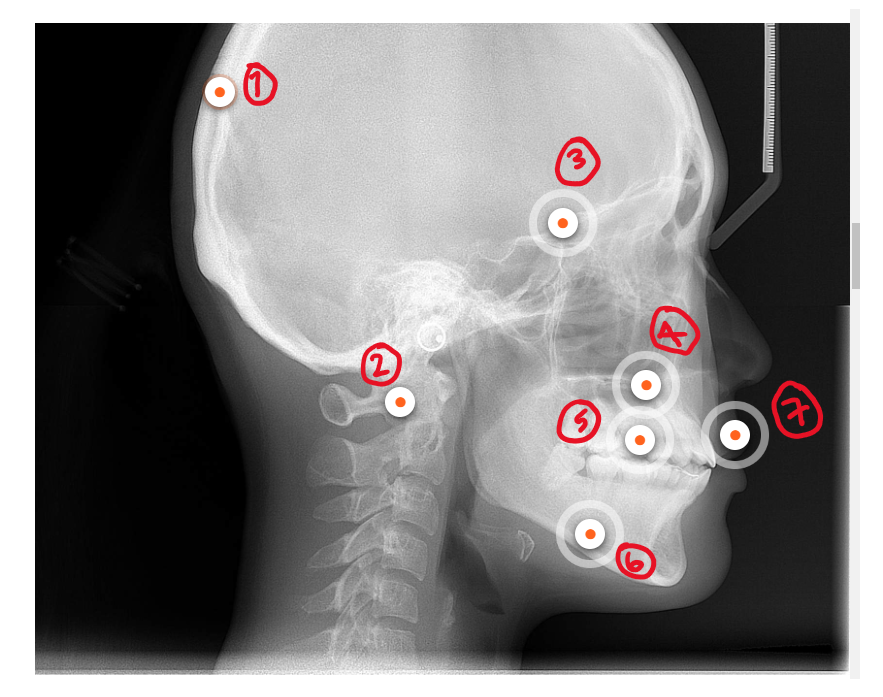

What’s 1?

Calvarium

What’s 2?

Cervical spine

What’s 3?

Cranial base